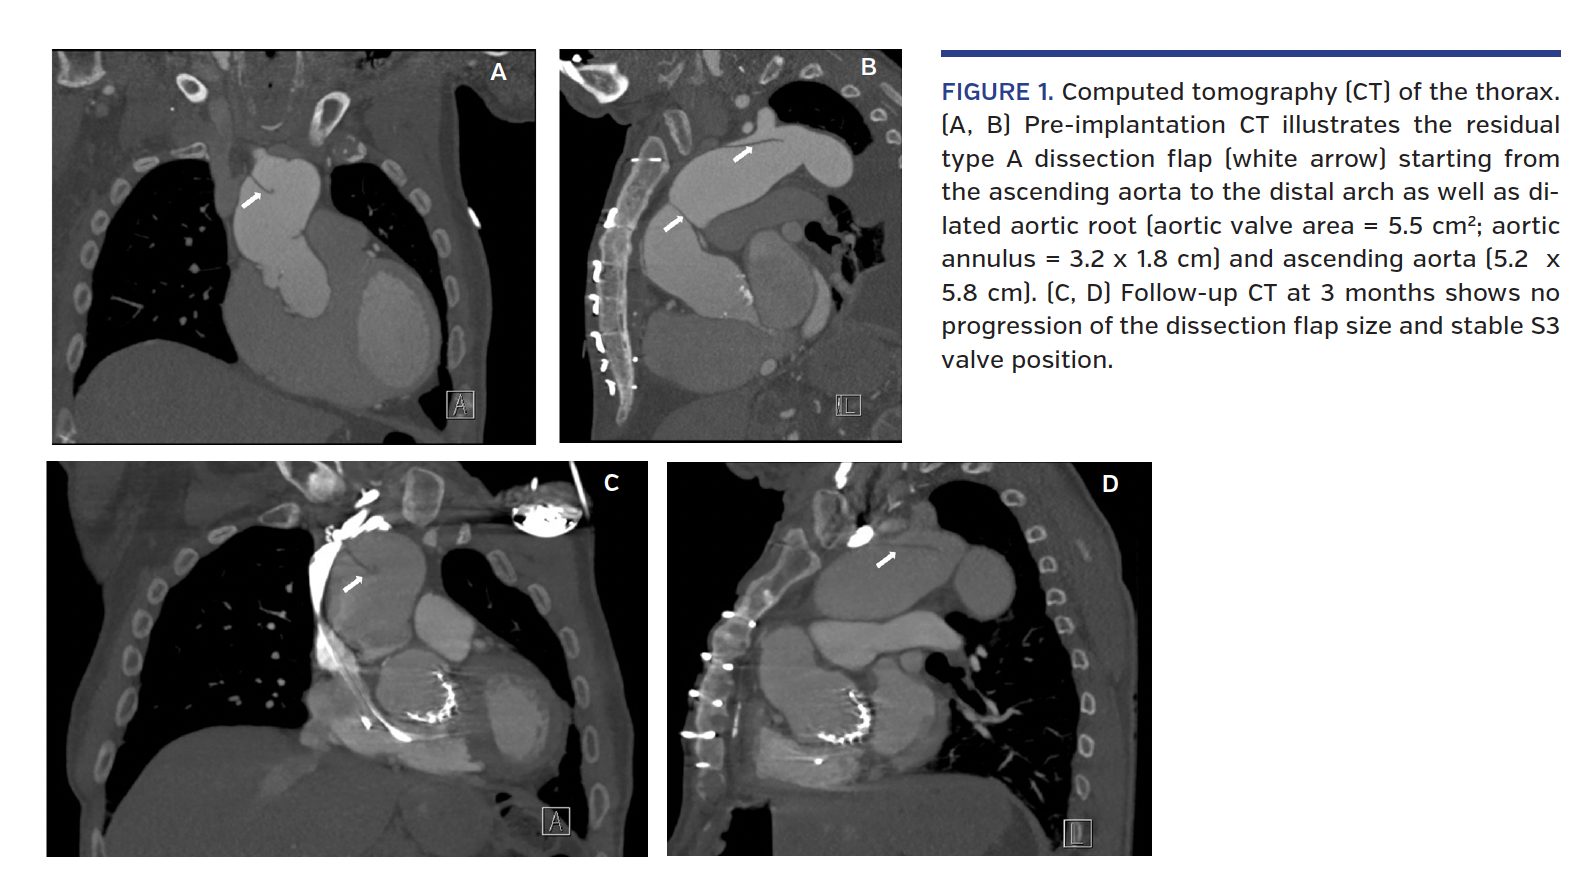

A 74-year-old male with ascending aorta repair 15 years ago sparing the native valve and ascending aorta (no aortic graft was used) following type A aortic dissection presented with symptomatic severe native aortic valve regurgitation. Computed tomography (CT) thorax scan showed a residual type A aortic dissection flap starting from the ascending aorta and ending in the distal arch with significant dilatation of the aortic root and ascending aorta (Figures 1A and 1B).

Repeat CT of the thorax at 3 months confirmed no change in the size of the dissection flap or aortic dimensions with stable valve position (Figures 1C and 1D) and the patient’s symptoms were much improved.